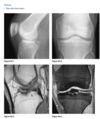

Q

A 19-year-old man with pain in the left knee

A

Anteroposterior (Fig. 2.16.1) and lateral

(Fig. 2.16.2) radiographs of the left knee show a semi-

circular lucency, with an adjacent bony fragment,

on the lateral aspect of the medial femoral condyle

(arrows).

sagittal T2-weighted MR

image in the same patient demonstrates minimal

linear increased signal intensity in the same region

as the lucency, located between the subchondral

bone and the fragment (Fig. 2.16.3, arrow). The frag-

ment has low signal intensity and is not completely

covered by cartilage.

Osteochondritis dissecans (osteochon-

drosis) of the medial femoral condyle

from an osteochondral fracture

that was initially caused by shearing, rotatory, or

tangentially aligned impaction forces.

The presence of linear high T2-weighted

signal intensity between the fragment and donor site

indicates fluid or granulation tissue and strongly sug-

gests instability of the fragment (i.e., loose in situ

fragment) (Fig. 2.16.4, arrowheads). Focal cystic areas

beneath the fragment or denudation of articular carti-

lage are also MR signs suggesting an unstable fragment.

All patients with radiographic evidence of osteochon-

dritis dissecans could potentially benefit from MRI to

assess the integrity of the donor fragments before any

surgical or arthroscopic intervention or therapy (71).